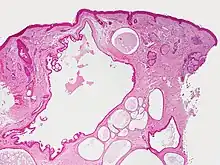

Hidrocystoma (also known as cystadenoma,[1] a Moll's gland cyst,[1] and a sudoriferous cyst[1]) is an adenoma of the sweat glands.[2]: 787

Hidrocystomas are cysts of sweat ducts, usually on the eyelids.[3]: 664 They are not tumours (a similar-sounding lesion called hidroadenoma is a benign tumour).

Hidrocystomas usually arise from apocrine glands. They are also called cysts of Moll or sudoriferous cysts. A type of hidroadenoma that arises from eccrine glands is uncommon.